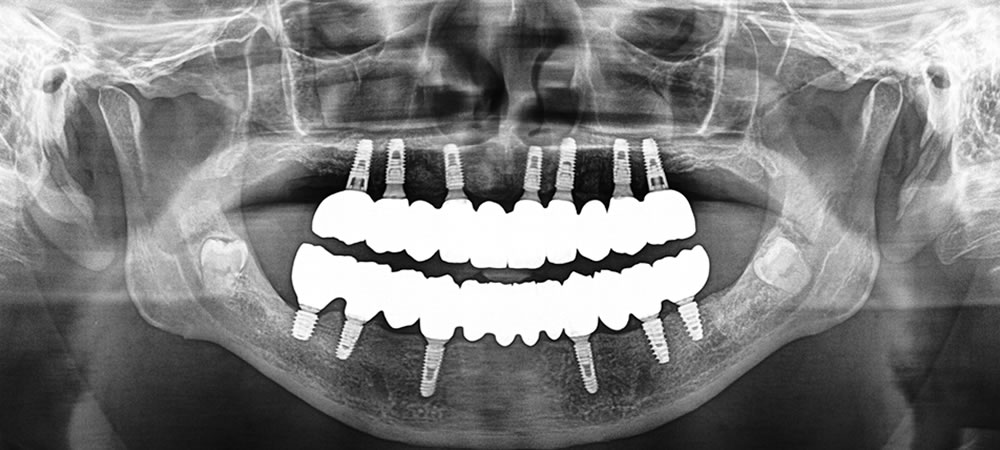

顎骨は必要量残っていたため、抜歯と同時にインプラントを埋入し、当日に仮歯まで装着する抜歯即時荷重インプラントを選択しました。

保存不可能な歯を抜歯し、シミュレーション通りの位置へインプラントを埋入した後、予め製作しておいた固定式の仮歯を装着しました。

最後方の臼歯部は重度歯周病だったため、ソケットリフトを行い、ティッシュレベルインプラント(インプラントの土台が歯茎の上に出るタイプ)を埋入しました。

固定式の仮歯を3ヵ月以上使用していただき、よく噛めるか、食べ物が流れるか、歯磨きはしやすいかなどを確認した後、最終的なジルコニアの上部構造へ変更しました。

最終的なジルコニアの上部構造へ変更した後、全体的な咬み合わせを調整して治療完了となりました。